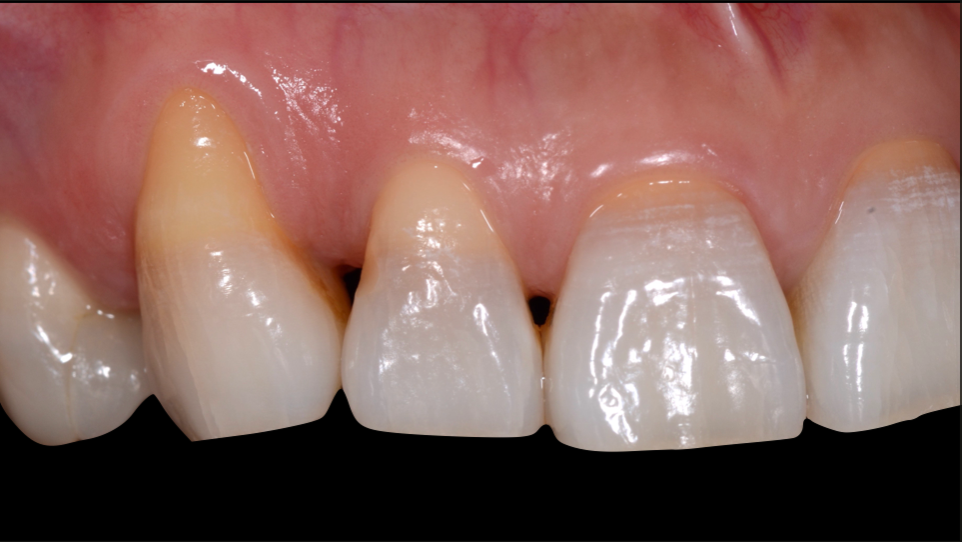

ガミースマイルを歯周形成外科で改善し、笑顔を取り戻した症例

- 年代、性別 30代・女性

- 来院動機 ガミースマイルを治したい

- 治療内容 歯周形成外科